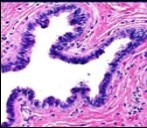

Alternatively, cutaneous ciliated cyst can be lined by non ciliated cuboidal or columnar epithelium with intermingled intercalated, dark or round peg cells. Foci of squamous metaplasia can be occasionally exemplified in the adherent epithelium whereas mucinous cells or apocrine-like features are exceptional 6, 8. Figure 1, Figure 2, Figure 3, Figure 4, Figure 5, Figure 6, Figure 7, Figure 8, Figure 9, Figure 10, Figure 11, Figure 12. 11, 12, 13, 14, 15, 16, 17, 18, 19.

Figure 2.Ciliated cutaneous cyst with an undulating layer of ciliated cuboidal epithelium and supporting fibrous tissue framework (12).